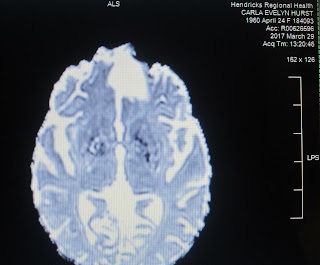

Putnam County Hospital stabilized me and did a CAT scan.

and run my yearly MRI.

Chris has the disk...going to pull off images soon...and have a follow-up scheduled with my doctor on the 13th.

The gist of the whole business seems to be that FRED

(the fat bastard)

has taken it upon himself to squidge and squash a bit more space

for himself and apparently he smushed a bit of

brain tissue that ought not be squidged.

FRED 2017 ( that white blob on the right crossing over midline...which is actually my left)

Close up of the Cerebellar Degeneration (twiggy area)

that has effectively destroyed my gait.

The upside to the neoplastic disorder is that the antibodies

have also kept the tumor size increase minimal for

almost 10 years now...and therefore me alive.

Undamaged Cerebellum for Comparison)